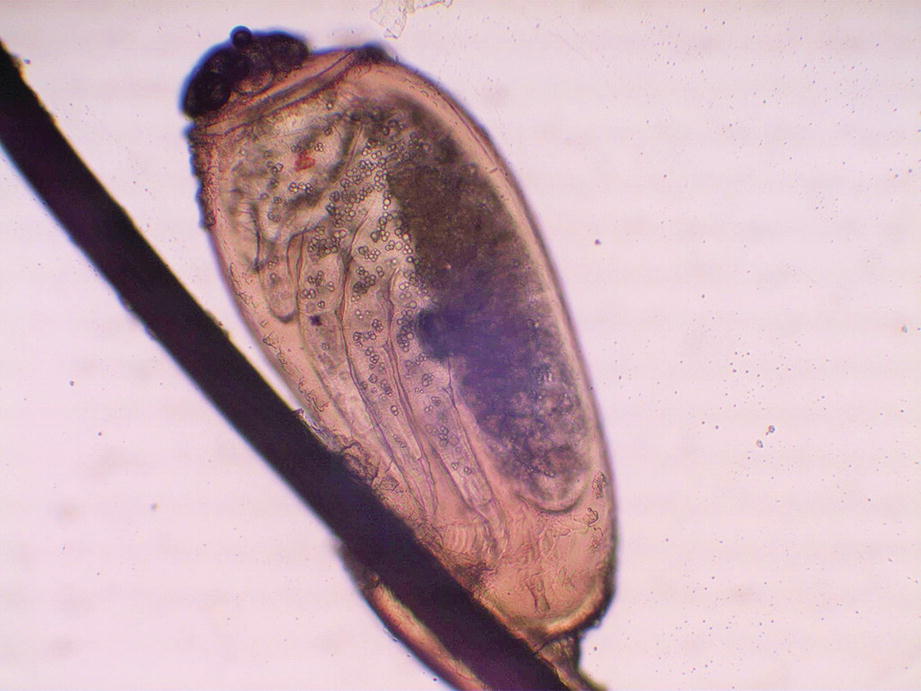

Pediculosis nit (chlorazol black 40×)